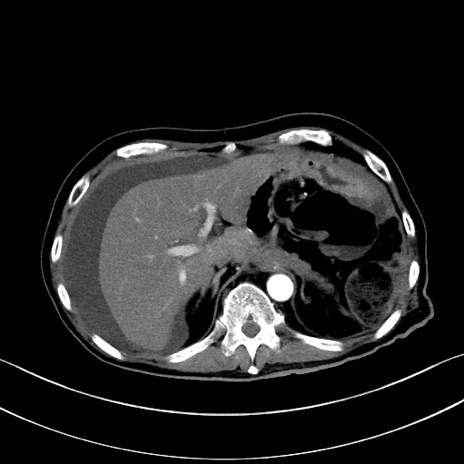

症例28(横断像)

【症例】60歳代男性

【主訴】嘔吐

【現病歴】胃癌にて胃全摘後。食思不振が悪化し、夜中に嘔吐することがある。

【既往歴】胃癌、胃全摘、脾摘、胆摘後

【データ】WBC 5900、CRP 10.56